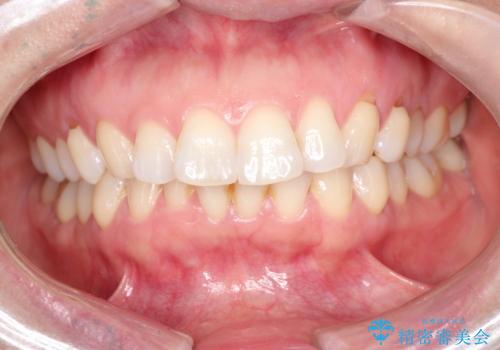

前歯と奥歯のガタガタを矯正で改善

- 患者様は、前歯と奥歯のガタガタ(叢生)を改善し、正面から見た時の歯並びを美しく整えたいとのご要望で来院されました。診断の結果、非抜歯での矯正が可能と判断し、インビザラインを使用する治療計画を立案しました。透明な矯正装置で目立ちにくい治療を行いながら、前歯と奥歯の両方を整列させることを目標にしました。

インビザラインを用いて、前歯の見た目を重視しつつ、奥歯のガタガタも改善しました。特に正面から見た際の美しい歯列を意識し、段階的に歯を移動させることで、全体の調和を図りました。治療中は、適切な装着時間を守ることや、装置の清潔を保つことが重要でした。また、歯肉や歯列全体に無理な負担がかからないように移動を管理しながら治療を進めました。結果として、前歯と奥歯がきれいに並び、見た目にも機能的にも満足いただける仕上がりとなりました。